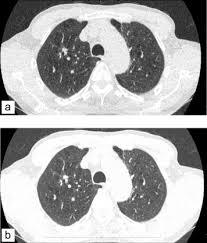

Scanner Thoracique Quelles Indications Fiches Sante Et Conseils Medicaux

Scanner Thoracique Quelles Indications Fiches Sante Et Conseils Medicaux from sante.lefigaro.fr

Informations importantes sur le scanner thoracique : Pourquoi passer un scanner thoracique ? Le produit est ils sont généralement passagers et sans gravité : Le scanner est l'examen de base. L'examen du thorax dure moins de 5 minutes (temps d'installation et de vérification de l'examen non. Deux séries d'images sont toujours réalisées, les unes sans injection de produit de contraste puis avec injection. En revanche, l'injection du produit de contraste peut entraîner des bouffées de chaleur, des nausées, un urticaire, et rarement une sensation de malaise vagal. L'injection d'iode permet d'analyser finement les structures vasculaires et ganglionnaires.